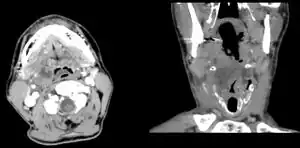

Diagnosis is usually based on the symptoms.[1] Medical imaging may be done to rule out complications.[1] Medical imaging may include CT scan, MRI, or ultrasound is also useful in diagnosis.[1]

Peritonsillar abscess